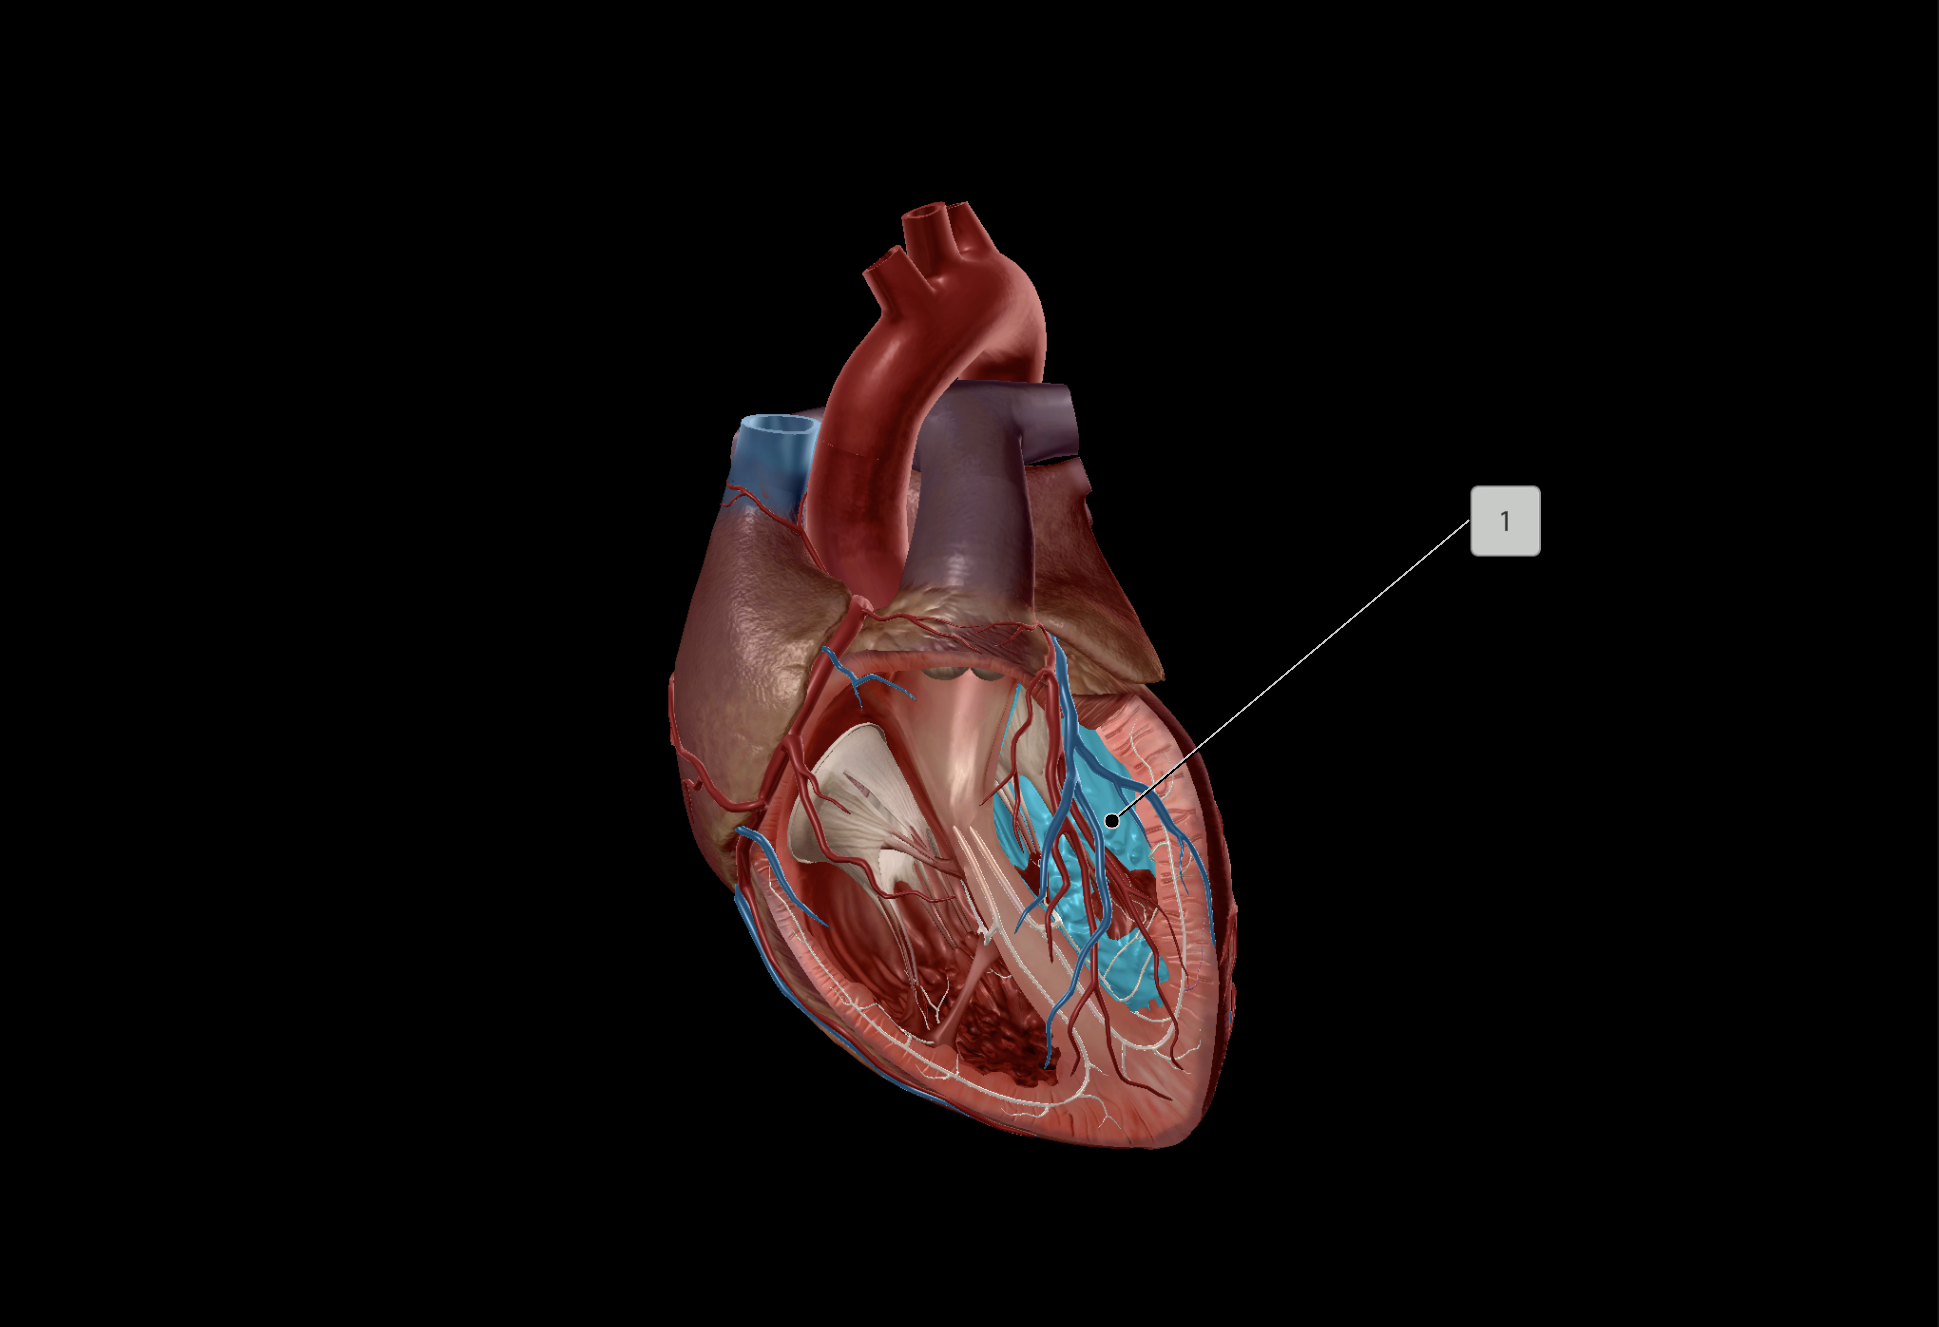

Left Ventricle

Right Ventricle

Bicuspid Valve

Papillary Muscle

Chordae Tendineae

Middle Cardiac Vein

Coronary Sinus

Small Cardiac Vein

Anterior Cardiac Vein

Coronary Veins

Great Cardiac Vein